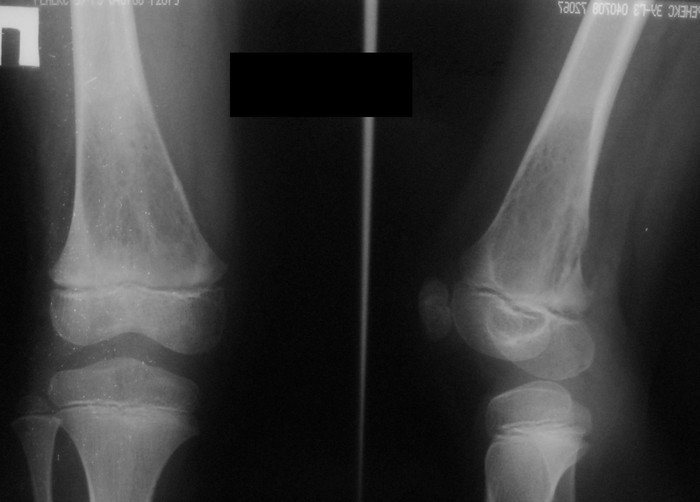

Уважаемые коллеги,

3 месяца назад в отделении была прооперирована девочка 7 лет с

клинико- рентгенологической картиной аневризмальной кисты (открытая

биопсия). Гистологическое заключение местных гистологов и ФНКЦ им. Д.

Рогачева -аневризмальная киста. 2 недели назад девочка взята на костную